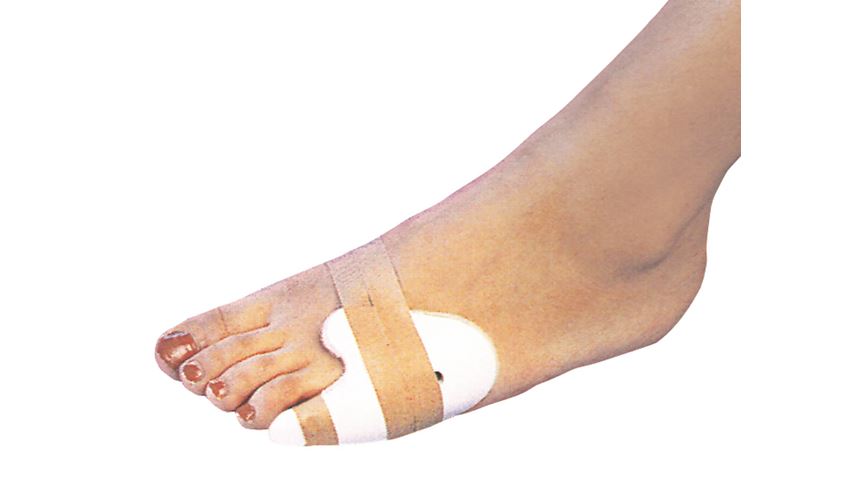

새끼발가락 골절: 스플린트·버디테이핑

왜 스플린트가 유용한가

- 작은 뼈 세 개가 얇게 붙어 있어 정밀 깁스보다 가볍고 효율적

- 인접 발가락과 묶어 충격 흡수

버디테이핑 단계

- 깨끗이 세척 후 건조

- 의료용 테이프 2.5cm 폭, 8 자(∞) 형태로 두 발가락 묶기

- 발바닥 아래 거즈 패드 삽입해 압력 분산

- 2‒3일 간격으로 테이프 교체